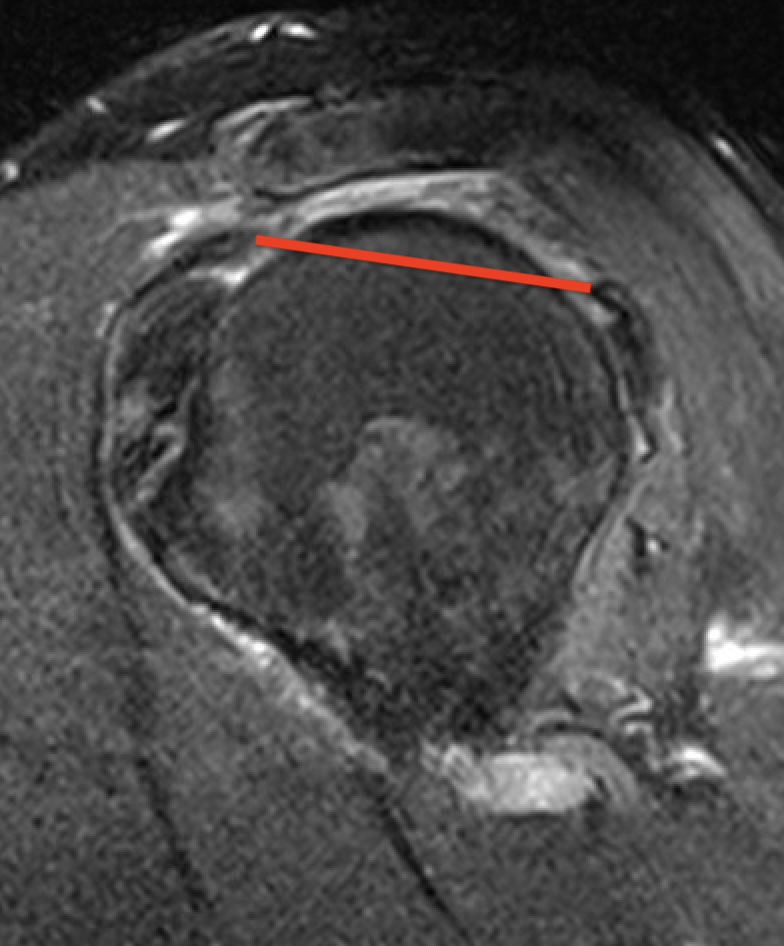

Supraspinatus atrophy

Tangent sign

- sagittal MRI

- line connecting superior coracoid and superior border scapular spine

- if supraspinatus muscle is below line, there is significant atrophy

- positive tangent sign / significant atrophy associated with larger tears / irrepairable tears

Negative tangent / no atrophy Positive tangent / significant supraspinatus atrophy